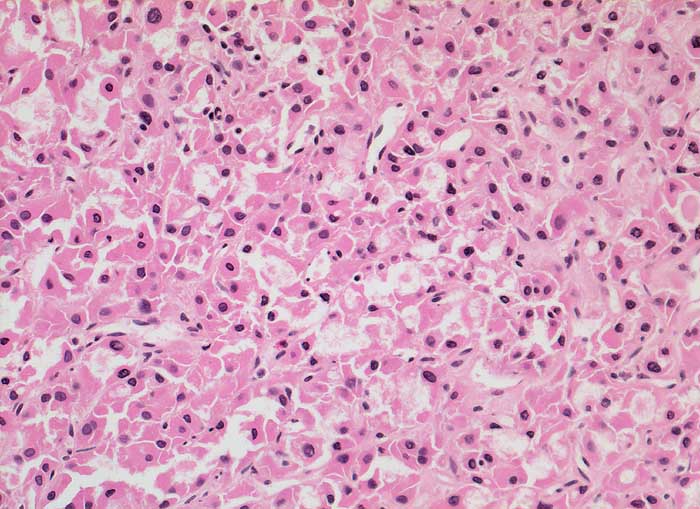

p/ Onkozytäres Schilddrüsenkarzinom

Onkozytäres Schilddrüsenkarzinom

Ausgeprägte Kernpolymorphie, Nukleolenatypie und unscharfe Zytoplasmagrenzen der oxyphilen Zellen sind Malignitätszeichen. Eine Unterscheidung von onkozytären Adenomen und Karzinomen ist zytologisch aber nicht sicher möglich.

Gezeigt werden zwei Fälle von histologisch gesicherten onkozytären Karzinomen.